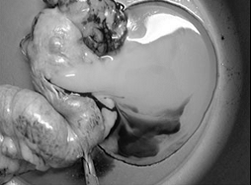

Матка (uterus, hystera, s. metra) представляет собой непарный мышечный орган, заключающий в себе полость (cavum utеri), в которой происходит развитие плода, затем - изгнание его наружу в процессе родового акта. У псовых (Canidae), к которым относится собака (Canis familiaris), матка двурогого типа (uterus bicornis), многоплодная. Анатомически на ней принято различать парные рога (соrnu uteri), непарные тело и шейку. Топографически матка располагается в тазовой полости дорсально по отношению к мочевому пузырю и вентрально по отношению к прямой кишке. Вдаваясь краниальной частью в поясничную область перитонеальной полости. Рога беременной матки опускаются в подвздошные и паховые области, а при количестве плодов более шести достигают подреберной области мечевидного хряща (рис. 1, 2).

рис. 1. Строение беременной матки собаки. Экспонат из коллекции анатомического музея МГАВМиВ.